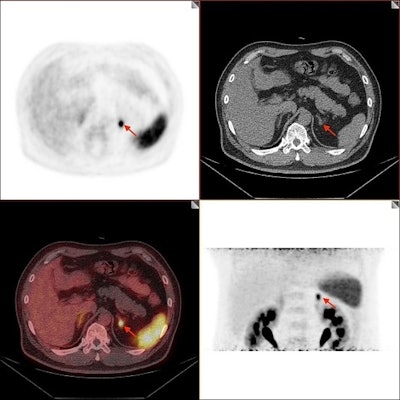

Image of positive adrenal lesion with small size. A 59-year-old male PA patient with one small size lesion in left adrenal gland was identified as positive by Ga-68 pentixafor PET/CT, with a SUVmax of 7.7 and a diameter of 0.8 cm. This patient achieved both complete clinical and biochemical success after laparoscopic total adrenalectomy and result of pathological diagnosis was aldosterone-producing adenoma. Images available for republishing under Creative Commons license (CC BY 4.0 DEED, Attribution 4.0 International) and courtesy of the Journal of Clinical & Translational Endocrinology.Image of positive adrenal lesion with small size. A 59-year-old male PA patient with one small size lesion in left adrenal gland was identified as positive by Ga-68 pentixafor PET/CT, with a SUVmax of 7.7 and a diameter of 0.8 cm. This patient achieved both complete clinical and biochemical success after laparoscopic total adrenalectomy and result of pathological diagnosis was aldosterone-producing adenoma. Images available for republishing under Creative Commons license (CC BY 4.0 DEED, Attribution 4.0 International) and courtesy of the Journal of Clinical & Translational Endocrinology.